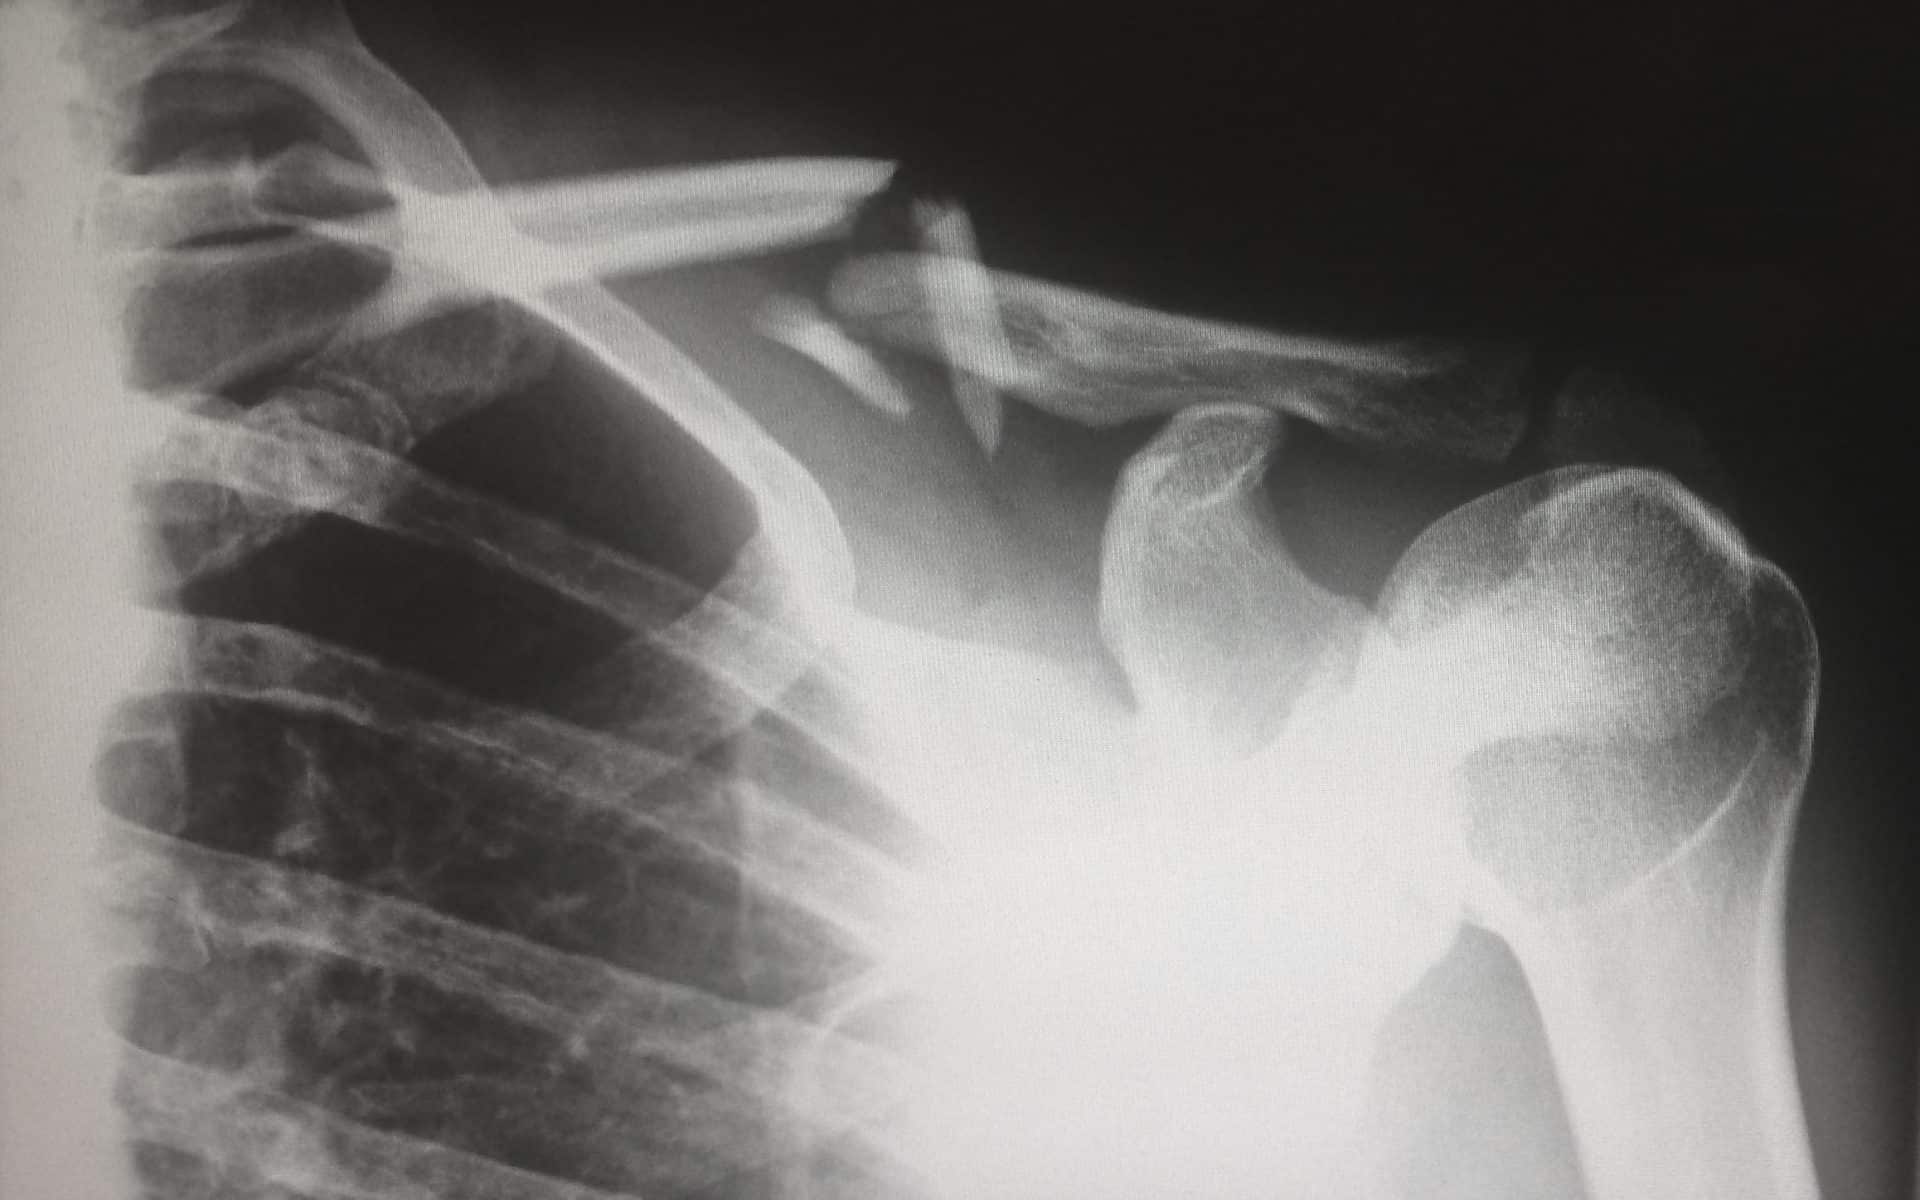

While on assignment in Ohio, Ricky suffered a devastating fall from a roof. Unfortunately, Ricky remains in the hospital and has a long road to recovery ahead.  The mounting expenses have taken a financial toll. Given the circumstances, the family has set up a GoFundMe page, which is available here – https://www.gofundme.com/funds-for-rickyEberl has pledged to match donations up to $10,000.00.